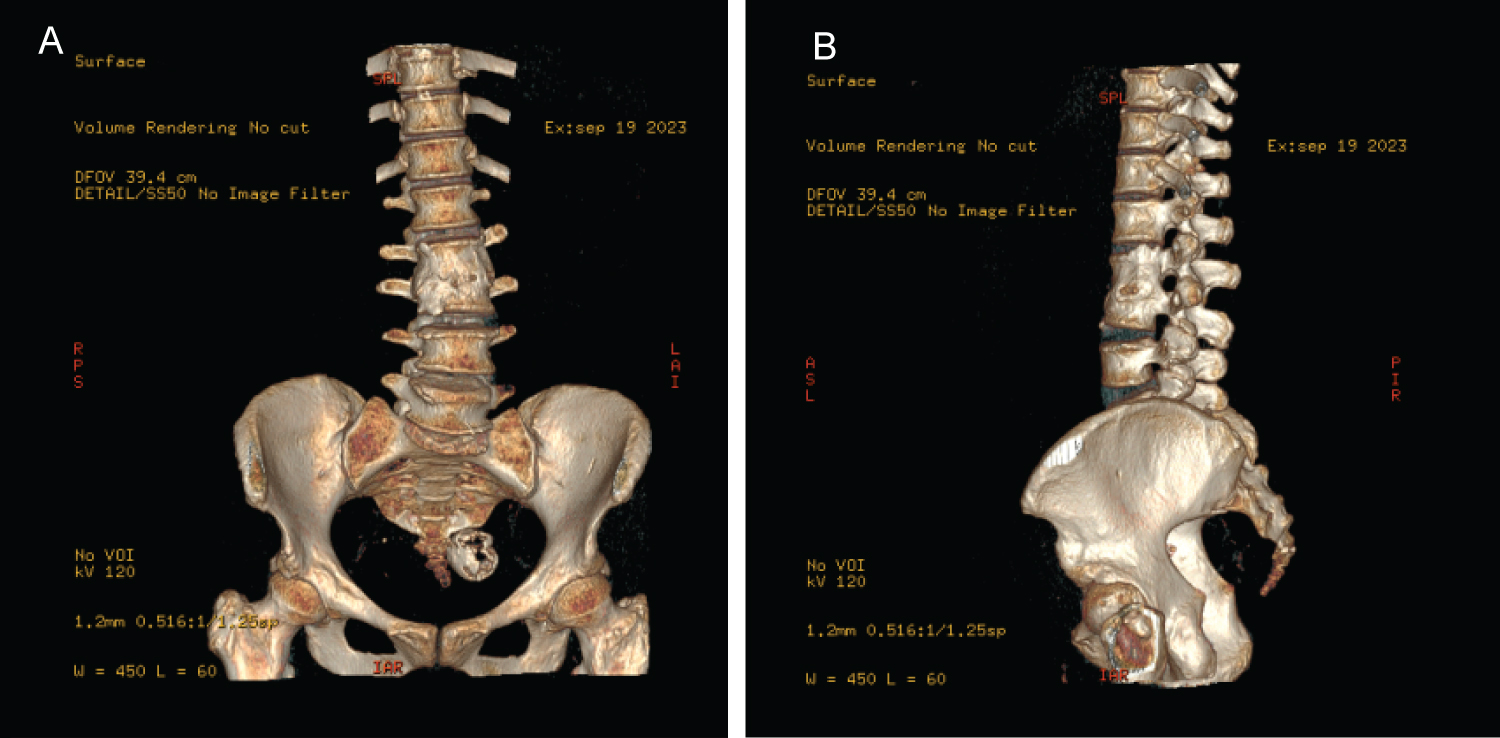

Figure 3: (A,B) 3-dimensional (3D) tomographic reconstruction, image A AP view, Image B Lateral view. In both images, the consolidation between the L2 and L3 vertebral bodies can be corroborated. View Figure 3